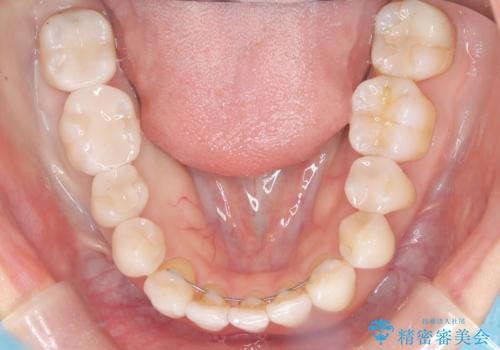

- 主訴:下の歯に入っている銀歯が笑うと目立つので白くしたい。

下顎臼歯部に入っている保険適用のメタルインレー(4箇所)を、審美性・適合性・清掃性の良いセラミックインレーにてやり替えました。